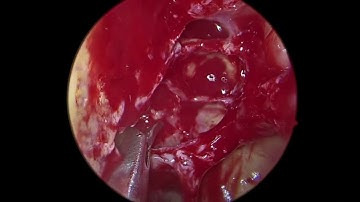

(B) CRSsNP Pus in all Sinuses (B) FESS Under LA